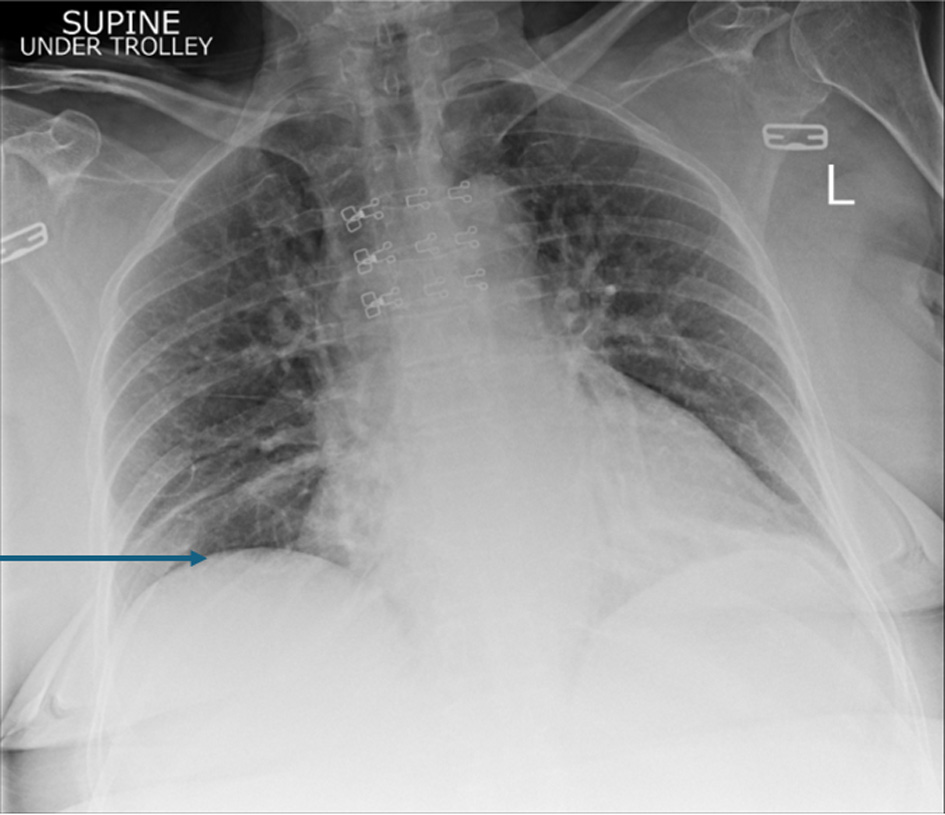

On examination, the patient was found to have externally rotated and shortened left leg and bilateral lower leg edema. Initial abdomen examination revealed soft non-tender abdomen. X-ray imaging of pelvis revealed subcapital fracture of the left neck of femur. She was afebrile (36.4 °C) with heart rate of 68 bpm, oxygen saturation of 97%, and blood pressure of 170/89 mm Hg. On auscultation, the chest was clear bilaterally with a midline trachea and no crepitus. The patient was subsequently diagnosed with non-traumatic neck of femur fracture and underwent hemiarthroplasty of the left leg under general anesthetic. Postoperative examination of the patient revealed soft non-tender but distended abdomen with absent bowel movement. The patient reported no discomfort, but it remains unclear whether this is due to postoperative analgesia or her continuing pregabalin use. Her postoperative analgesia included codeine 30 mg four times a day with breakthrough oral morphine 10 mg as required. The patient opened her bowels on postoperative day 2. Initial supine chest radiograph (CXR) revealed shallow lung expansion with elevated hemidiaphragms more in the right side (Fig. 1), compared with CXR performed 3 years ago which was normal (Fig. 2). Repeat anterior-posterior chest radiograph conducted the second day postoperatively showed gas filled loops of bowel beneath the hemidiaphragms with a distended bowel (Fig. 3). Although pneumoperitoneum was the primary concern, it was crucial to rule this out using both clinical and imaging studies. It remained unclear whether a small bowel obstruction or an abscess was present in X-ray. Computed tomography (CT) was conducted which revealed interposition of bowel between the liver and diaphragm which is consistent with Chilaiditi sign and small compressive atelectasis in the lung basis. The CT scan ruled out the presence of any abnormal bowel dilation, pneumoperitoneum, and abdominal mass (Fig. 4). The patient received medical optimization for bone protection, intensive physiotherapy, and occupational therapy input. She was discharged 13 days postoperatively with twice-daily care support. Reports in her 3-month outpatient orthopedic review remarked on her good recovery. No specific follow-up for her Chilaiditi syndrome was required and her recovery from this was uneventful.

Figure 4. Confirmed Chilaiditi, normal variant with normal appearances of the solid abdominal organs. No dominant lymphadenopathy. No free fluid. No pelvic mass. Images taken day 1 postoperatively.